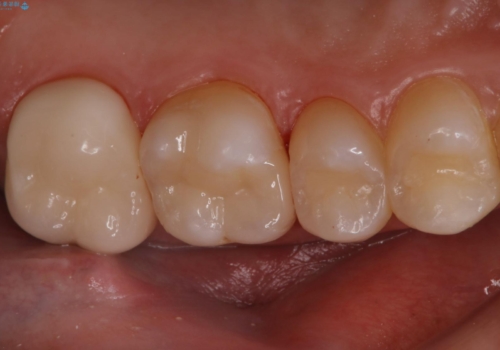

セラミックインレーとクラウンで歯ぐきの腫れを治す

金属を除去し、虫歯の治療後に型取りを行い、清掃性、審美性に優れたセラミックインレー、セラミッククラウンを装着いたしました。

新しい被せ物が入った後は、歯肉の腫れはなくなり、定期検診の際もプラーク等の貯留もみられなくなりました。